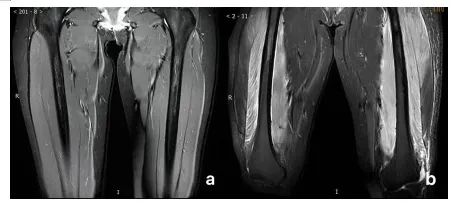

MR检查可评估横纹肌溶解的严重程度

(图a为正常大腿MR表现;图b为横纹肌溶解综合征患者的双侧大腿MR表现)